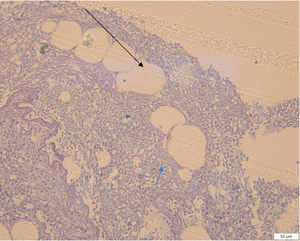

Market-size fish. Granulomas were observed in peritoneal adipose tissues located between the inner organs. Granulomas had soft capsules and contained oil vacuoles with cell debris or were empty (Figure 4). The capsule wall consisted of fibroblasts and fibers. Rarely did the small count of granulomas become gold-brown due to the presence of ceroid. No inflammation was found in the peritoneal cavity or the inner organs of fish.